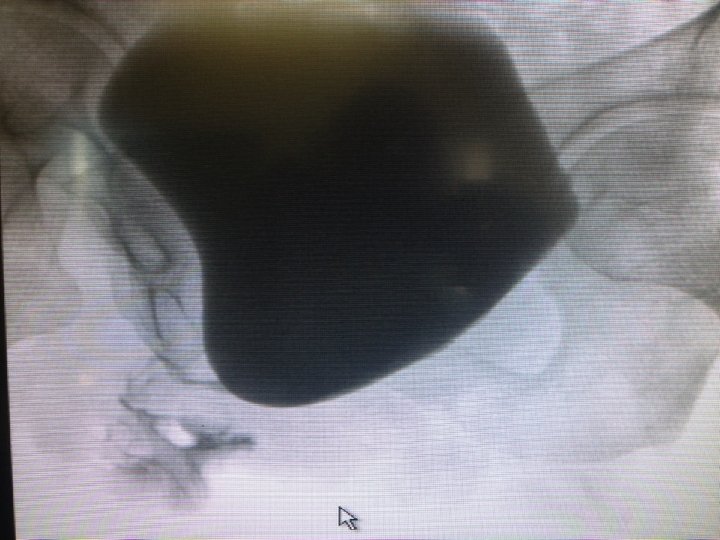

Other radiological tests: Cystogram